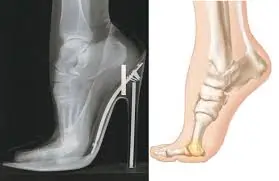

મોબિલિટી એક્સરસાઇઝ (Mobility exercises) આધુનિક ફિટનેસ અને રિહેબિલિટેશન (પુનર્વસન) દિનચર્યાઓનો એક આવશ્યક ભાગ બની ગઈ છે. ભલે તમે રમતવીર હોવ, ફિટનેસના શોખીન હોવ અથવા બેઠાડુ જીવનશૈલીને કારણે જડતાનો સામનો કરી રહ્યાં હોવ, તમારી ગતિશીલતા (mobility) સુધારવાથી તમારા જીવનની એકંદર ગુણવત્તામાં નોંધપાત્ર વધારો થઈ શકે છે. સાચા અર્થમાં ફક્ત સ્ટ્રેચિંગ કરવા કરતાં અલગ, મોબિલિટી એક્સરસાઇઝ સાંધાની…